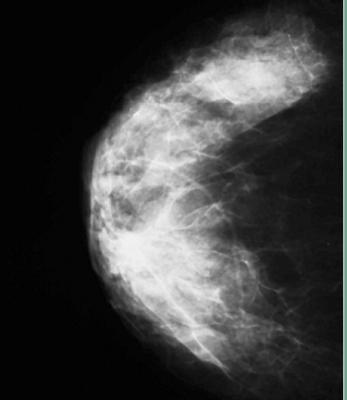

VolparaDensity helps radiologists objectively assess density from both digital mammography and tomosynthesis images to help doctors evaluate who might benefit from additional screening. Highly correlated to breast magnetic resonance (MR) assessments, VolparaDensity automatically generates an objective measurement of volumetric breast density correlated to the ACR breast composition categories.